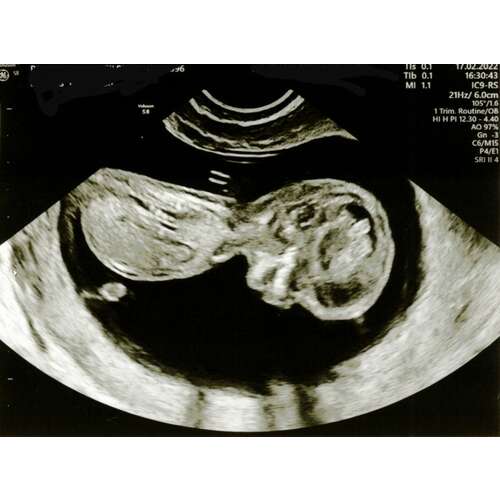

Hoi hoi! Ben super benieuwd wat jullie denken. Echo 13+3 💖💙?